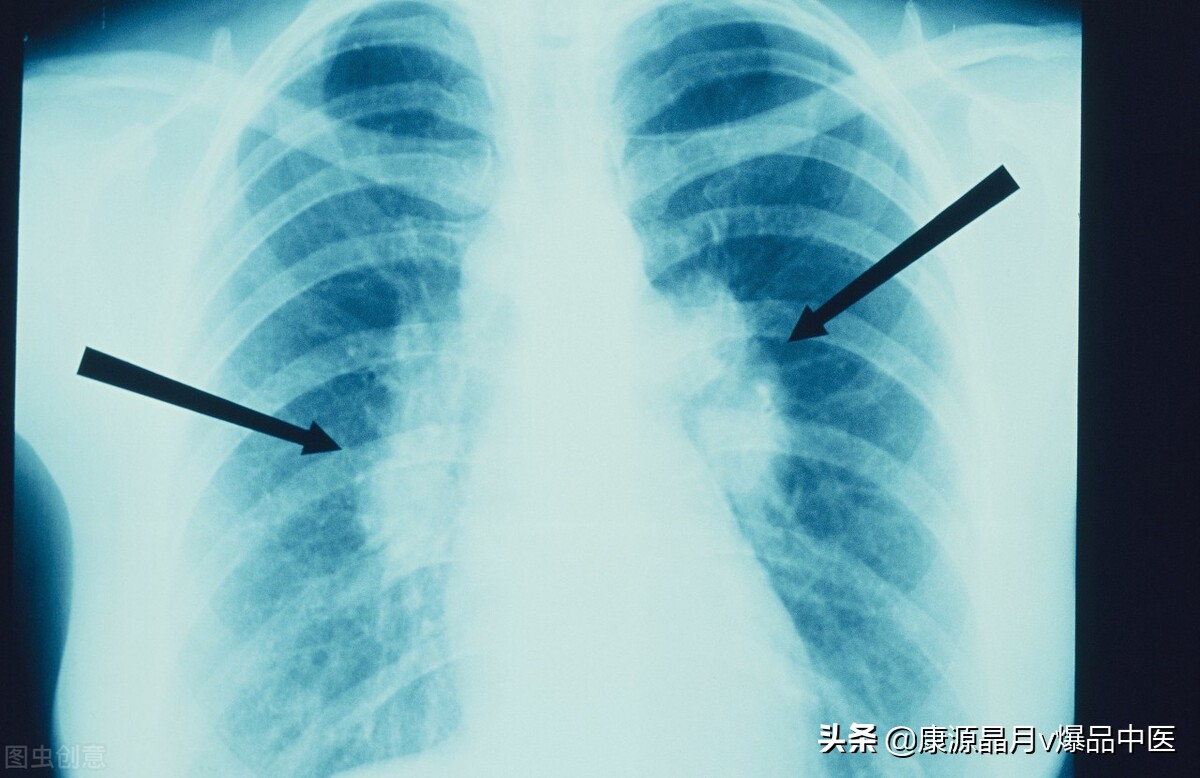

10肺病:尺泽神水能止咳,太渊有鱼更治喘;更有肺俞天突穴,咳喘逢之如泼雪。